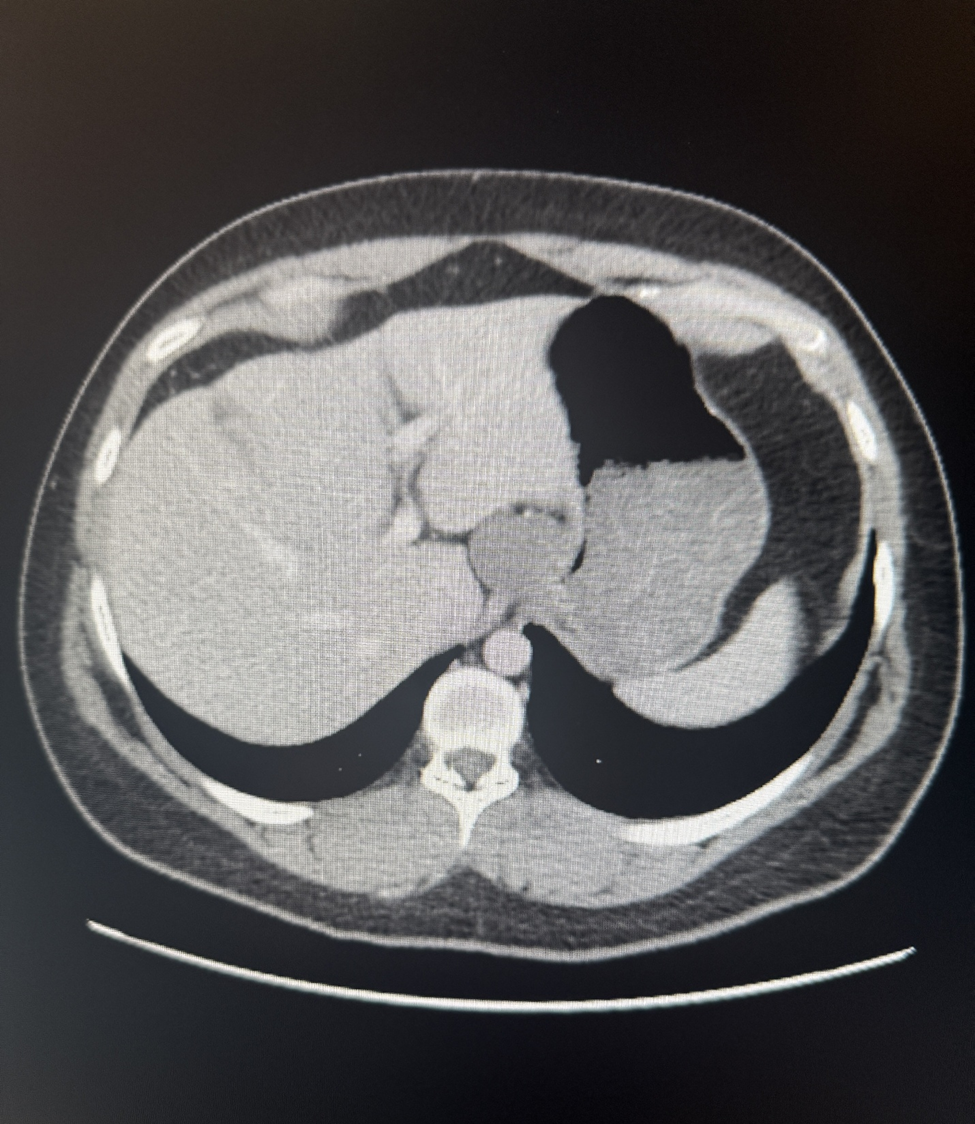

A 28-year-old healthy gentleman with no prior medical history presented to the emergency room with sudden onset of severe right upper quadrant and epigastric abdominal pain associated with nausea and vomiting. Liver enzymes and lipase were normal. CBC showed mild leukocytosis (12.24 K/microL).  Cross-sectional imaging revealed a well-circumscribed soft density lesion adjacent to the gastroesophageal junction (Fig. 1). Ultrasound evaluation did not show any cholecystitis or gall stones. Esophagogastrostomy did not show significant changes in the esophagus or in the gastroesophageal junction or in the stomach. Endoscopic ultrasound evaluation showed a well encapsulated lesion measuring 3 cm not arising from the muscularis propria of the esophagus but close to the GE junction with both liquid and solid contents (Fig. 2). Needle aspiration showed mucinous material suggesting possible esophageal duplication cyst.  Laparoscopy was performed ,revealing a pedunculated  cystic lesion at the gastroesophageal junction (Fig. 3). It was stapled at its origin, with a bougie in the esophagus to minimize the risk of narrowing the esophageal lumen (Fig. 3). Histopathological examination confirmed it was indeed an esophageal duplication cyst (Fig. 4,5 &6). The inner lining of the cyst was ciliated columnar epithelium (Fig. 4). Interestingly double layer of smooth muscle was noted (Fig. 6). Following surgical removal, the pain completely resolved and on follow up the patient was feeling completely normal.

Figure 1. CT scan showing the lesion adjacent to the GE junction